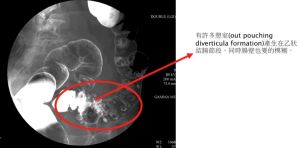

大腸的憩室是屬於假性憩室,其黏膜以及黏膜下層穿越肌肉層向外鼓出,存在以久的憩室,會發生顯微性的穿孔造成糞便的外滲,而後周邊的發炎。

在急性期或初期來說,鋇劑大腸攝影及結腸內視鏡並不建議,可能會並發腹膜炎或腸穿孔的可能。再著電腦斷層可以在有腫瘍的患者上直接作經皮引流。